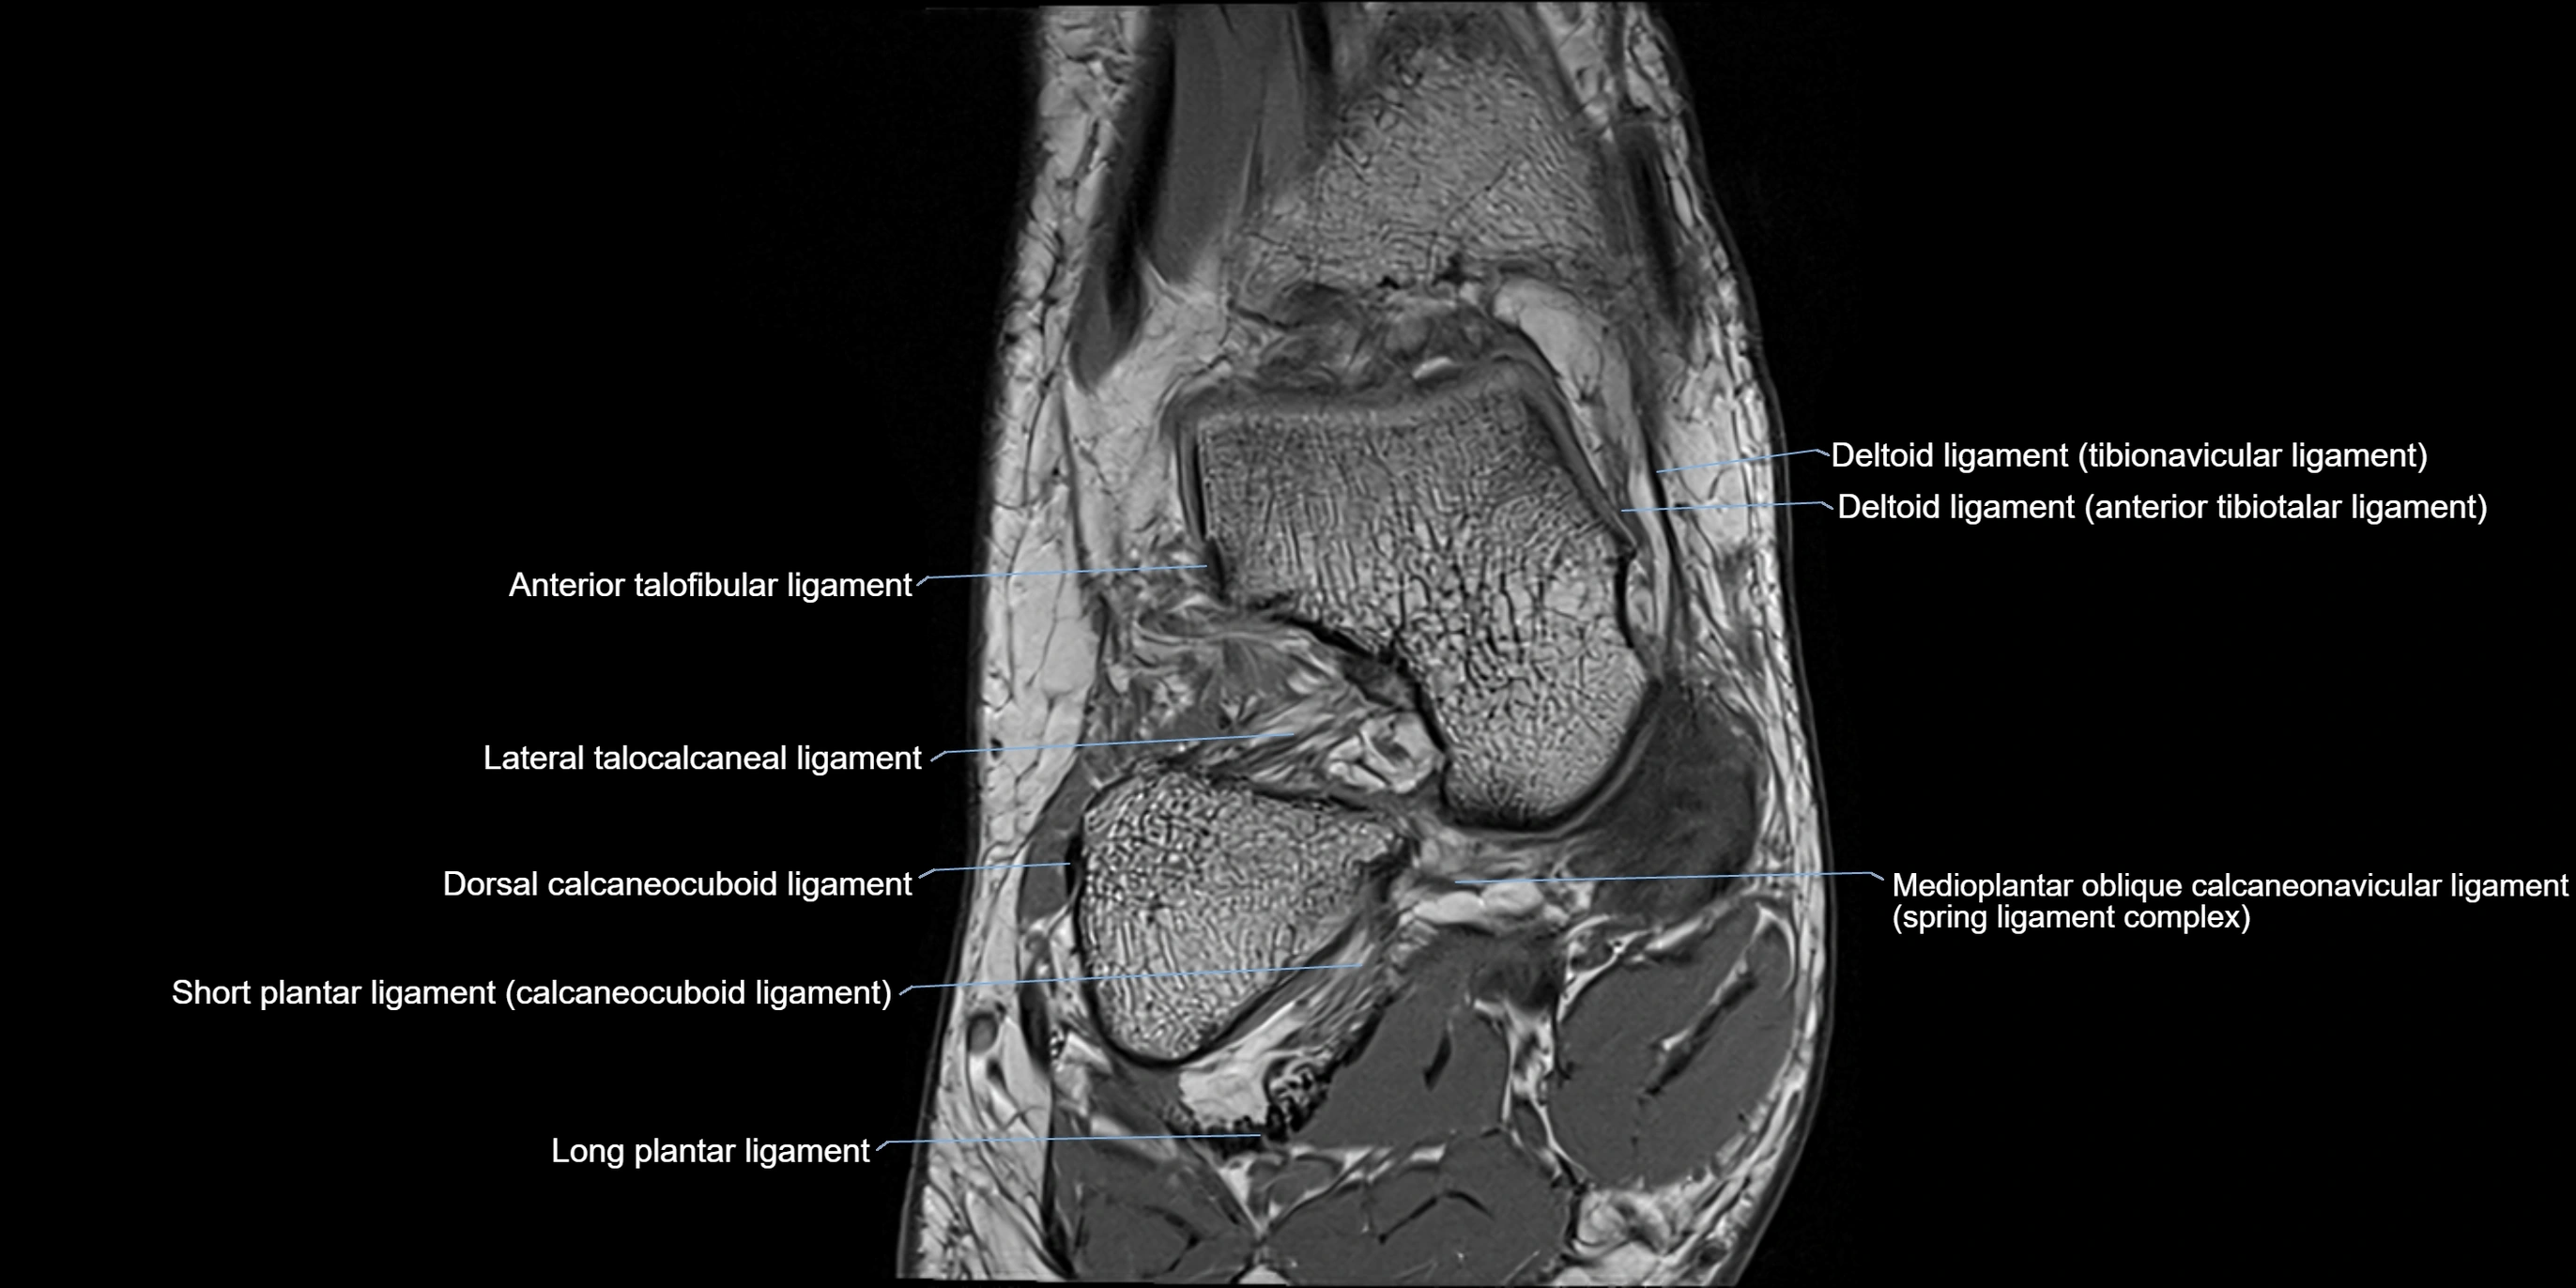

MRI image

image